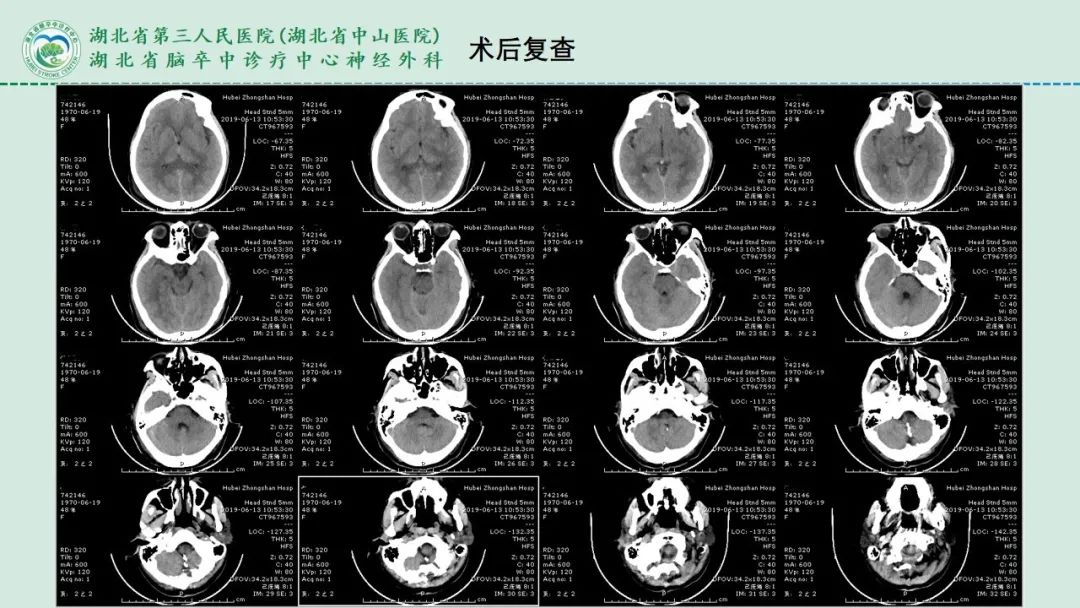

李俊教授团队:右侧PICA延髓扁桃体段多发动脉瘤

今日与大家分享的是《正海-妙术视界》第二百三十二期,由湖北省第三人民医院李俊教授团队带来的右侧PICA延髓扁桃体段多发动脉瘤,欢迎观看、分享。